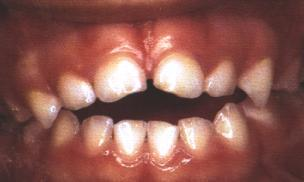

Τα περισσότερα παιδιά σταματούν αυτή τη συνήθεια από μόνα τους στην ηλικία των 2-4 ετών. Ωστόσο, υπάρχουν περιπτώσεις όπου ο θηλασμός του δαχτύλου ή της πιπίλας συνεχίζεται εντατικά για μεγαλύτερες περιόδους. Αυτό έχει ως αποτέλεσμα να προκαλούνται διαταραχές στα δόντια (κενό- χάσμα ανάμεσα στα άνω και τα κάτω δόντια, χασμοδοντία) και στις γνάθους (προγναθισμός της άνω γνάθου, στενή άνω γνάθος), καθώς και προβλήματα στην ομιλία του παιδιού.